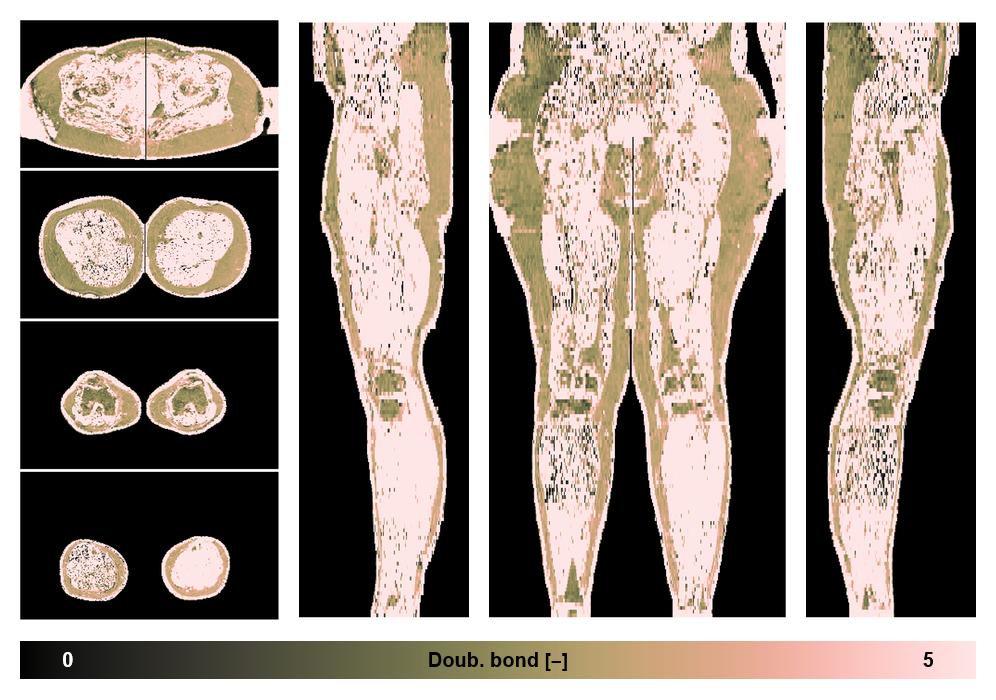

• Number of double bonds in subcutanious fat

Number of double bonds in subcutanious fat.